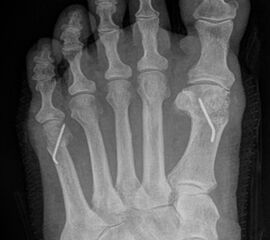

Abb. 3a, b: Präoperatives (a) und postoperatives (b) Röntgenbild bei Korrektur einer Typ I Deformität durch eine Exostosenabtragung.

Abb. 4a, b: OP Bilder bei lateraler Exostosenabtragung. Nach Hautschnitt ist die teilweise rupturierte laterale Gelenkkapsel erkennbar (a) mit Bursagewebe. Nach Resektion der Bursa und Abtragung der Exostose zeigt sich eine spongiöse Fläche (b) vor dem Wundverschluss.